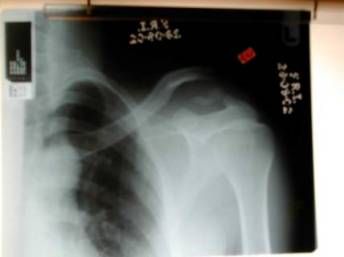

Broke mine in 2 places 11 weeks ago. Getting xray today to see if it has joined properly.

Rang them up cold after reading about then on here.... emailed them a copy of my xray ... "yeah we can fix that no probs" (or words to that effect)

sent for an x-ray

shows me the x-ray

Next time you're in there whip out you're iPhone and ask for permission to photograph the X-rays on his computer. You won't regret it

Broke my right (dominant) clavicle 6 weeks ago.

Very bad break, type 2, shortened with main bits pointing in different directions, very far apart with a nice sized fragment floating around at the front.

Luckily my friend is a physio, she got some other physios to have a look at the x-rays, they couldn't believe that I hadn't had it pinned.

Surgeon said the break was worse than it looked in the X-rays, the fragment of bone at the front was from around the back!